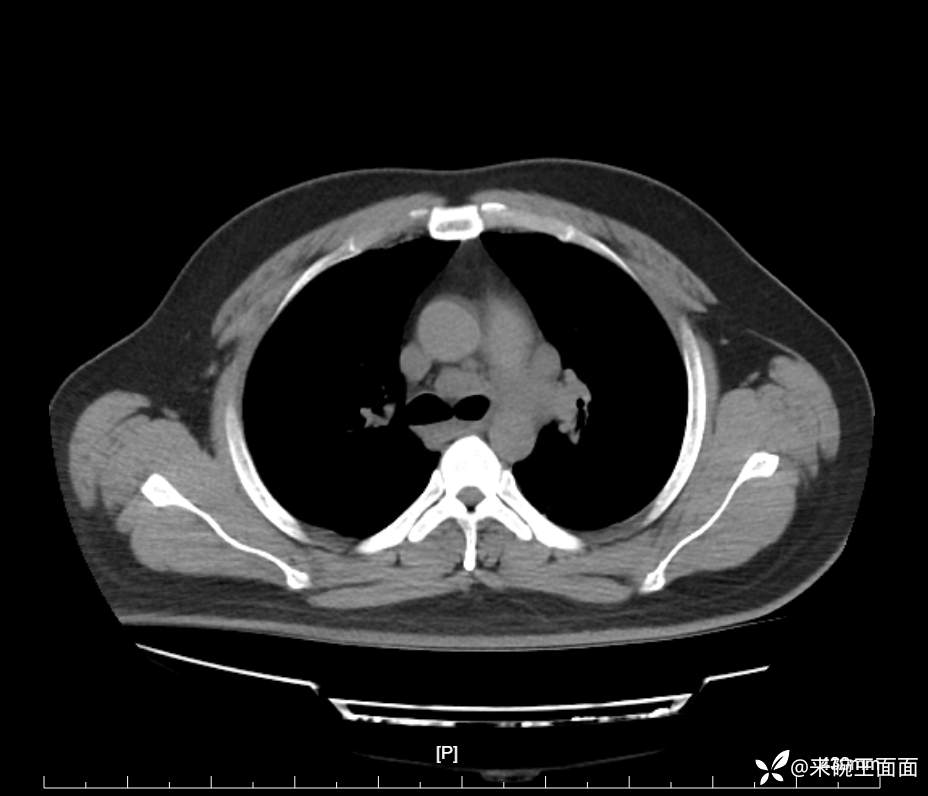

性别:男

年龄:27岁

主诉:胸闷胸痛数月余,休息后可自行缓解,无咯血症状。

个人史:数年吸烟史,具体不详。